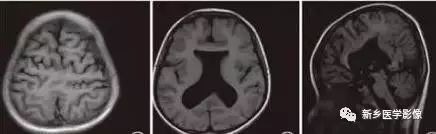

8.胼胝体发育不良

在脑发育腹侧诱导晚期,新形成的端脑嘴侧壁的背侧部分增厚、内陷,向后沿尚未完全发育的大脑半球间裂延伸。两个月后形成一个连合即胼胝体纤维的细胞框架,该细胞框架形成后胼胝体相应部分立即发育。膝部先发育。然后是体部、压部.位于胼胝体膝部后下方的胼胝体嘴最后发育。如果胼胝体发育过程中出现有害因素,就有可能导致胼胝体发育不良.表现为完全缺如或部分缺失。常表现为膝部存在或膝部和体部存在。压部和胼胝体嘴缺失。

胼胝体发育不良可见单独发病,但更常见的是伴有中枢伸经系统的其他畸形,包括胼胝体周围脂肪瘤、脑膨出、交通性脑积水Chaiarii畸形、Dandy-Walker囊肿、脑裂畸形等。临床上可无症状或仅有轻度临床症状,临床检查可见眼距过宽、大头畸形、智力发育迟滞等。胼胝体缺失时,MR冠状位上侧脑室前角呈新月形表现,侧脑室体部分离,呈垂直状平行走行。